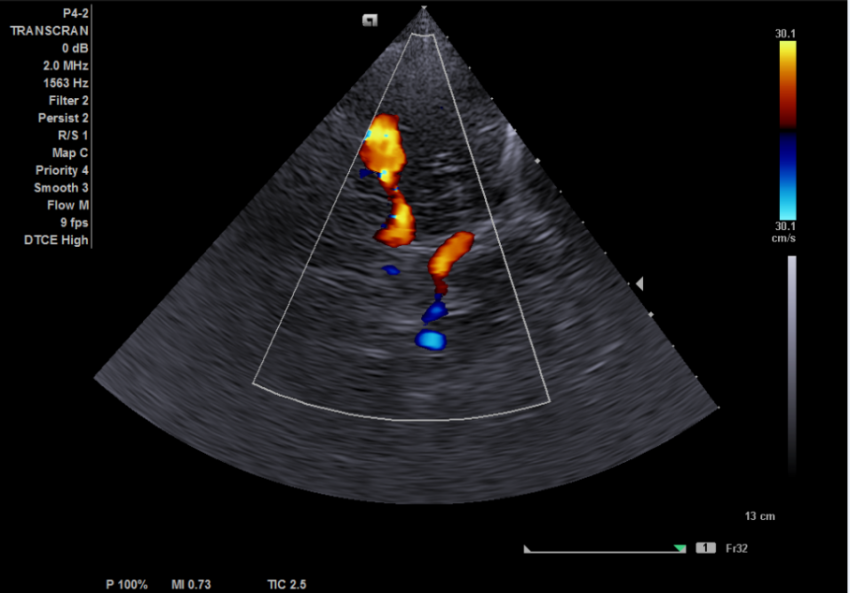

The examination is performed with a sector transducer through 'cranial windows', as these are the areas where bones of the skull are thinner and allow the best transmission of ultrasound. On the side of device, a good penetrating ability is provided by a stream of waves with low frequency. Since the higher the frequency, the faster the ultrasound wave attenuates, it is best to use transducers with a frequency of 1-6 MHz.

However, in order to obtain a diagnostically-appropriate image, one sensor with the appropriate frequency is not enough. You also need a machine with a good power which allows us to obtain an image with acceptable 2D resolution and high color Doppler sensitivity. We all know that machines are divided into different classes. In this article, we want to show you that for a good head vascular examination, it is not necessary to choose a premium class machine with an exorbitant price.

In terms of budget devices that are more affordable, the Siemens X150/300 has performed quite well in this particular area.